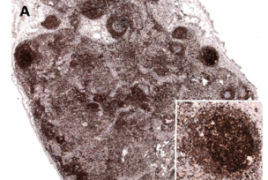

Follikulläres Lymphom (FL)

Das Follikuläre Lymphom gehört zu den B-Zell Non-Hodgkin-Lymphomen und ist durch die Translokation t(14;18)(q32;q21) charakterisiert, die zu einer konstitutiven Expression des anti-apoptotischen Proteins BCL2 führt. Des Weiteren ist das FL durch eine Vielzahl an sekundären genetischen Veränderungen gekennzeichnet, die in 70-90% der FL-Fälle gefunden werden.

Das Follikuläre Lymphom in situ (FLIS), das durch Studien der letzten Jahre als frühe Vorläuferform des FL gilt, aber nicht konsekutiv zum FL transformiert, zeigt die selbe Translokation wie das manifeste FL, doch fehlen diesem sekundäre genetische Veränderungen. Wir gehen davon aus, dass der Erwerb weiterer molekularer Alterationen für die maligne Transformation des FLIS in das manifeste FL notwendig ist. Ziel unserer Arbeit ist daher die Identifikation genetischer Veränderungen, die im FL und auch im FLIS bzw. nicht im FLIS vorliegen.

Wir verfügen über gepaarte Fälle mit FLIS und FL desselben Patienten und analysieren ausgesuchte Gene mittels Sequenzierung auf Mutationen. Darüber hinaus werden die Fälle mit Hilfe der array-Comparative Genomic Hybridization auf weitere numerische Aberrationen untersucht. Die aus dieser Studie hervorgehenden Daten könnten als Ansatzpunkt für neue Therapie-Ansätze genutzt werden, die darauf abzielen, die Entstehung des FL schon in frühen Stadien zu verhindern.